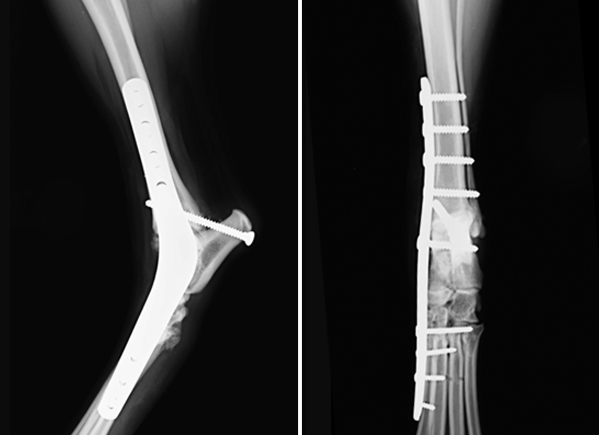

Остеосинтез коленного сустава

Остеосинтез коленного сустава 103 фотографий